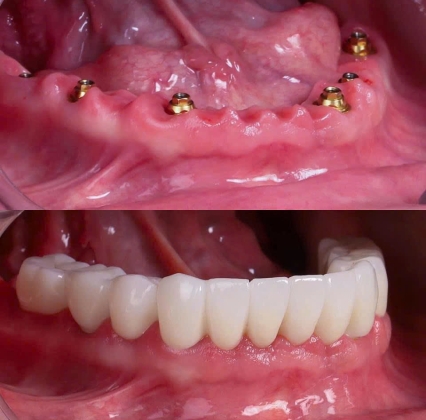

Cấy ghép Implant toàn hàm là giải pháp phục hồi răng hiện đại cho người mất răng toàn bộ. Tìm hiểu quy trình, lợi ích và điều kiện thực hiện tại Nha Khoa SV.

Cấy ghép Implant là phương pháp phục hồi răng mất hiện đại, giúp ăn nhai chắc chắn, thẩm mỹ tự nhiên, ngăn tiêu xương hàm. Tìm hiểu chi tiết tại Nha Khoa SV Quận 3.

Quy trình cấy ghép Implant tại Nha Khoa SV được thực hiện theo tiêu chuẩn y khoa, giúp phục hồi răng mất an toàn, bền chắc, ăn nhai như răng thật.

Tìm hiểu chi tiết quy trình cấy ghép Implant tại Nha Khoa SV: Từ khám tổng quát, đặt trụ Implant đến phục hình răng sứ. Cùng chuyên gia giải đáp các yếu tố ảnh hưởng đến quá trình trồng răng Implant an toàn, hiệu quả và bền vững.

Bài viết được viết bởi Bác sĩ phụ trách cấy ghép implant.Tại NHA KHOA SV, QUẬN 3. Thông thường, việc mất răng sẽ dẫn đến tình trạng tiêu xương hàm, tụt nướu, suy yếu các răng kế cận và cũng có thể làm mất đi nụ cười ở người bệnh. Theo truyền thống, phương pháp khắc phục tình trạng mất răng là sử dụng hàm răng giả và cầu chụp răng. Tuy nhiên hiện nay, implant được coi là lựa chọn tốt nhất để thay thế răng bị mất hoặc bị hư hỏng.